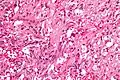

| Micrograph of a gangliocytic paraganglioma. H&E stain. | |

A gangliocytic paraganglioma is a rare tumour that is typically found in the duodenum and consists of three components: (1) ganglion cells, (2) epithelioid cells (paraganglioma-like) and, (3) spindle cells (schwannoma-like).[1]

GP consist of three components (1) ganglion cells, (2) epithelioid cells (neuroendocrine-like), and (3) spindle cells (schwannoma-like). The microscopic differential diagnosis includes poorly differentiated carcinoma, neuroendocrine tumour and paraganglioma.[1]